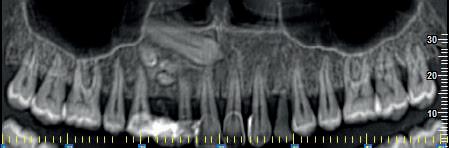

Un elemento dentale si definisce incluso quando il sacco follicolare non si apre in cavità orale in un periodo di tempo di circa 2 anni dopo la fisiologica epoca di eruzione e che ha perso la propria autonoma spinta eruttiva.

La diagnosi si avvale dell’osservazione clinica e della Diagnostica per immagini che consente di valutare eventuali cause che impediscono la fisiologica eruzione di un elemento dentale.

Il bilancio radiologico 3D fornisce al clinico informazioni utili relative ad ostacoli da rimuovere, all’orientamento del dente, ai rapporti con

strutture limitrofe, alla forma delle radici, a disarmonia dento-maxillofacciale, al rilievo di eventuali anchilosi del dente incluso.

La diagnostica per immagini si avvale di tecniche 2D (Ortopanoramica dentale e full endorale) e 3D (3D Cone Beam Computed Tomography - CBCT).

La 3D CBCT consente la perfetta localizzazione, posizione, versione del canino incluso, la valutazione dei rapporti con gli elementi dentali limitrofi ed eventuali contatti di allarme con le strutture anatomiche critiche (seno mascellare, CNP, fossa nasale, forcazione del premolare superiore).

Le notizie fornite al clinico sono necessarie nella pianificazione della terapia di disinclusione, che può essere ortodontica e/o chirurgica.

Nel presente articolo presentiamo 3 casi di inclusione del canino superiore.

Fig 2 : stesso Paziente. Ricostruzione panorex.

Il 13 è incluso per ostacolo di eruzione relativo alla presenza di minuti denticoli (odontoma composto).

In emiarcata sinistra, come reperto collaterale, si osserva persistenza di 63 ed agenesia di 23.